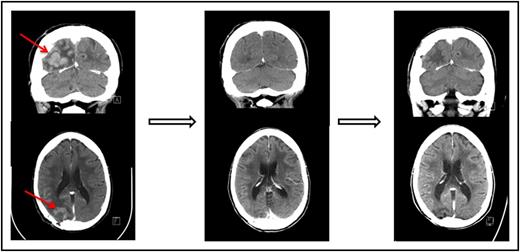

One of the patients who achieved a complete response to nivolumab had primary refractory PCNSL (Figure 1 and Table 1, patient 1). One patient who achieved only a partial response to prior WBRT had a further decrease in enhancing disease on nivolumab therapy (Table 1, patient 3). An additional patient who achieved only a partial response to prior focal radiation obtained a complete radiographic response to nivolumab with resolution of parenchymal and leptomeningeal involvement (Table 1, patient 5). This patient had persistent intraocular disease that was confirmed by vitrectomy and treated with ocular radiation (Table 1, patient 5).

Pre- and posttreatment head CTs with contrast in a patient with primary refractory PCNSL. (Left) The contrast-enhancing lesion before treatment with nivolumab. (Middle) Complete response following 2 months therapy with nivolumab. (Right) Continued complete response 13 months following initiation of therapy.

Pre- and posttreatment head CTs with contrast in a patient with primary refractory PCNSL. (Left) The contrast-enhancing lesion before treatment with nivolumab. (Middle) Complete response following 2 months therapy with nivolumab. (Right) Continued complete response 13 months following initiation of therapy.